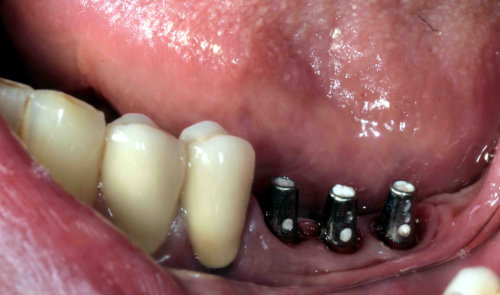

Implantate mit Aufbau für Kronen